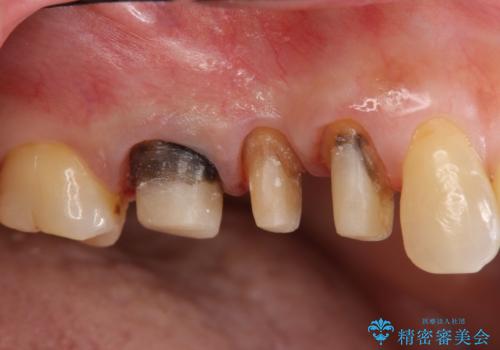

古くなったセラミッククラウンのやりかえ

- 老朽化し黒ずんできたクラウンのやりかえを希望され来院されました。

将来的に歯ぐきの位置が変化しても審美障害となりづらいオールセラミックジルコニアクラウンによるやり替えを計画します。